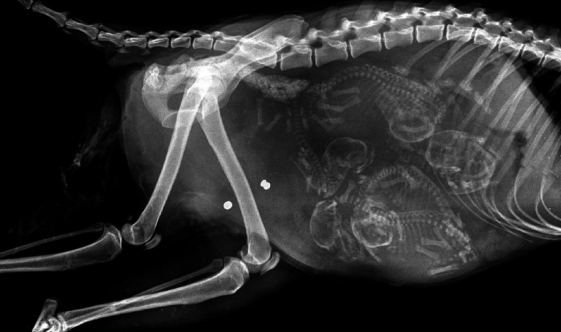

▼怀孕的猫咪